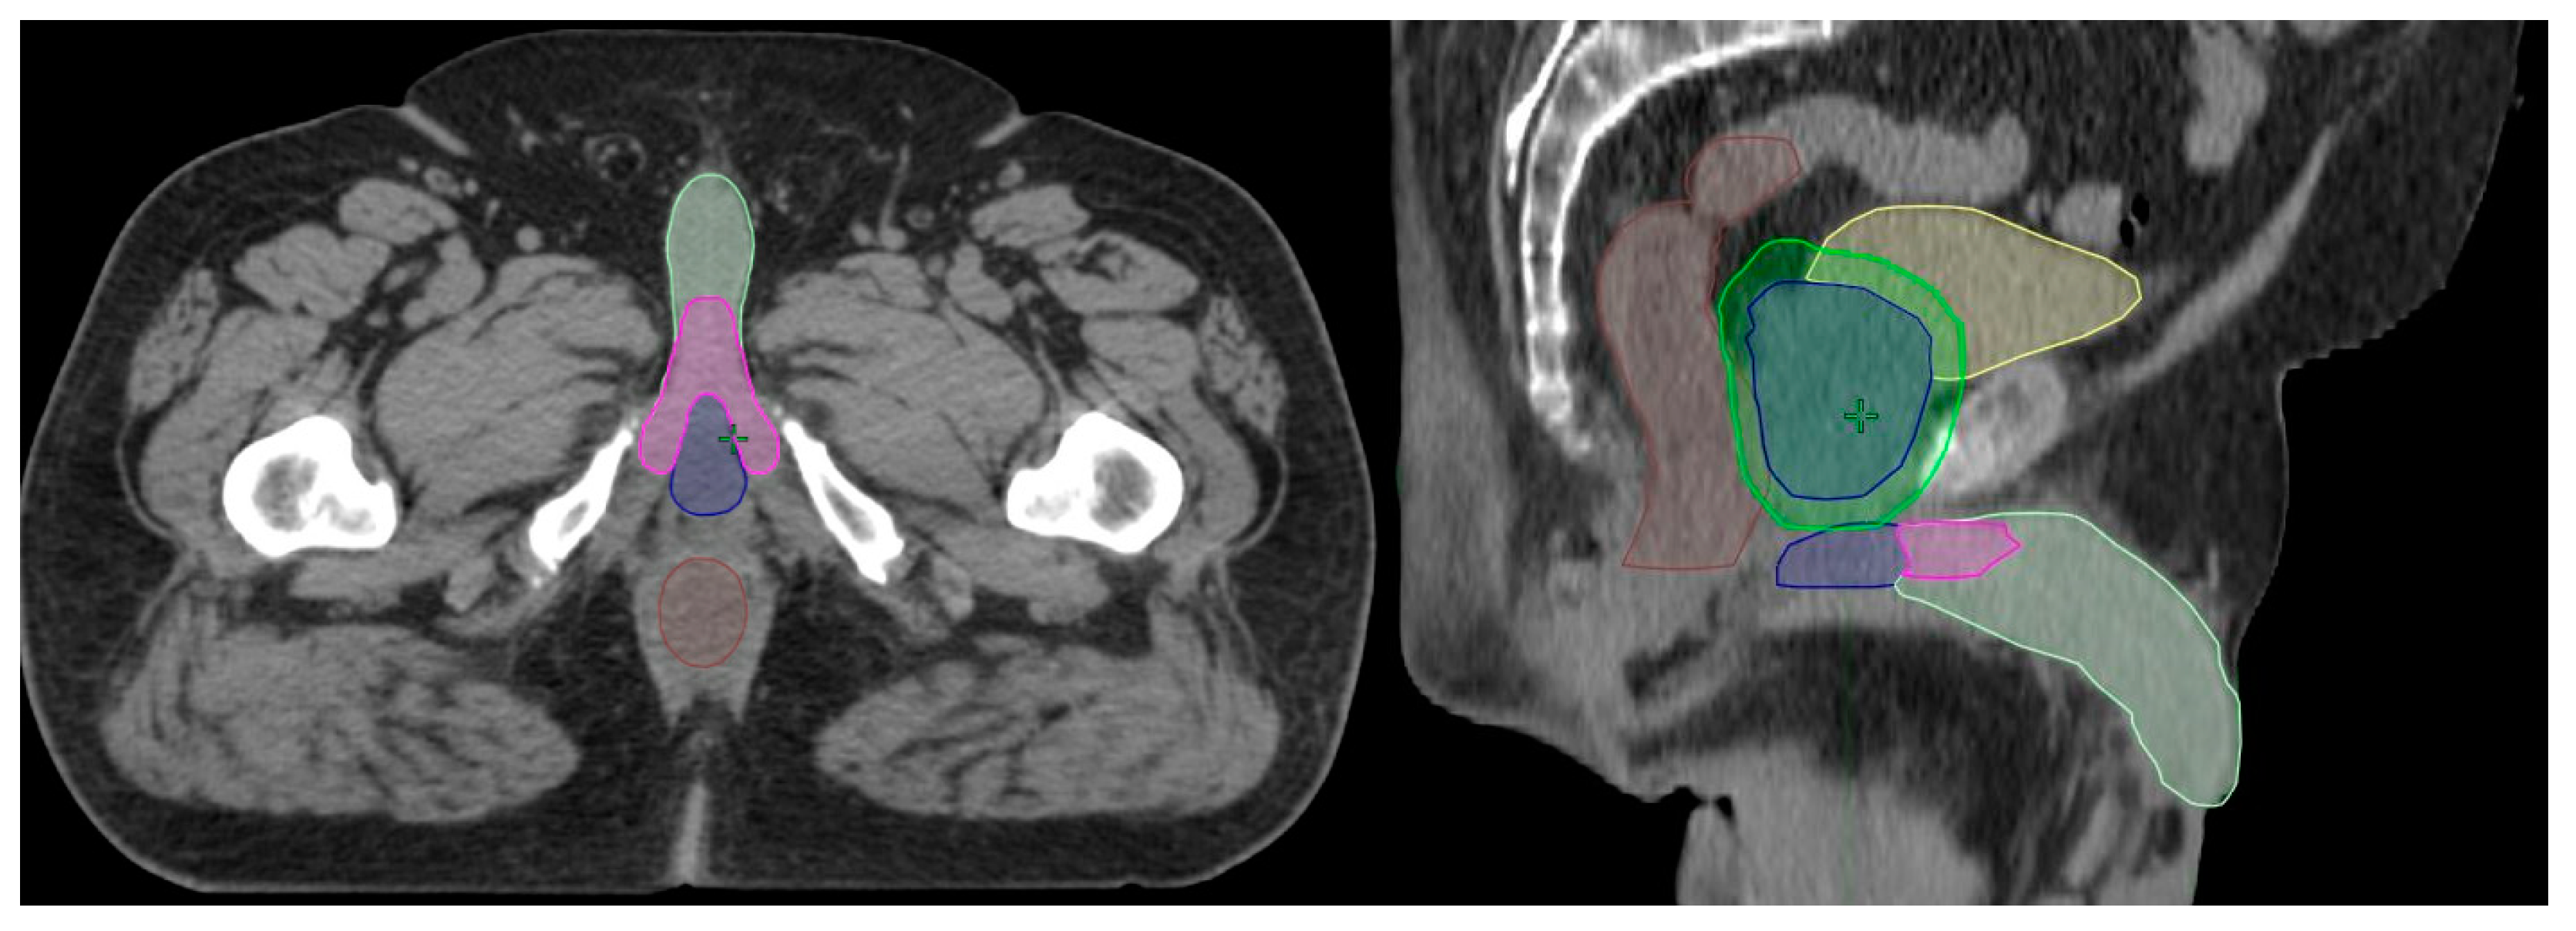

| Penile bulb volume [cc] | 4.7 (3.6–6.2) |

| Penile bulb mean dose [cGy] | 2490 (1529–3656) |

| Penile bulb V1000 cGy [%] | 73.5 (49–96.6) |

| Penile bulb V2000 cGy [%] | 49.1 (24.4–70.9) |

| Penile bulb V3000 cGy [%] | 34.9 (13.6–59.7) |

| Penile bulb V4000 cGy [%] | 22.6 (6.1–46.4) |

| Penile bulb V5000 cGy [%] | 11.8 (0.3–35.5) |

| Penile bulb V6000 cGy [%] | 1.6 (0–13.7) |

| Penile crus volume [cc] | 6.5 (5.1–8.5) |

| Penile crus mean dose [cGy] | 2095 (1306–3036) |

| Penile crus V1000 cGy [%] | 79.3 (49.9–98) |

| Penile crus V2000 cGy [%] | 42.6 (18.6–73.1) |

| Penile crus V3000 cGy [%] | 22 (4.5–47.9) |

| Penile crus V4000 cGy [%] | 9.6 (0.1–27.1) |

| Penile crus V5000 cGy [%] | 2.1 (0–11.3) |

| Penile crus V6000 cGy [%] | 0 (0–1) |

| Penile shaft volume [cc] | 93.3 (80.6–106.2) |

| Penile shaft mean dose [cGy] | 444 (313–650) |

| Penile shaft V1000 cGy [%] | 11.9 (6.9–19.8) |

| Penile shaft V2000 cGy [%] | 4.4 (1.8–8.6) |

| Penile shaft V3000 cGy [%] | 2 (0.4–4.1) |

| Penile shaft V4000 cGy [%] | 0.8 (0.1–2.1) |

| Penile shaft V5000 cGy [%] | 0.2 (0–0.9) |

| Penile shaft V6000 cGy [%] | 0 (0–0.1) |